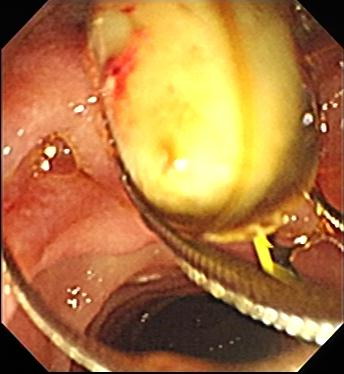

胆总管内金属支架置入后 胆总管内金属支架置入